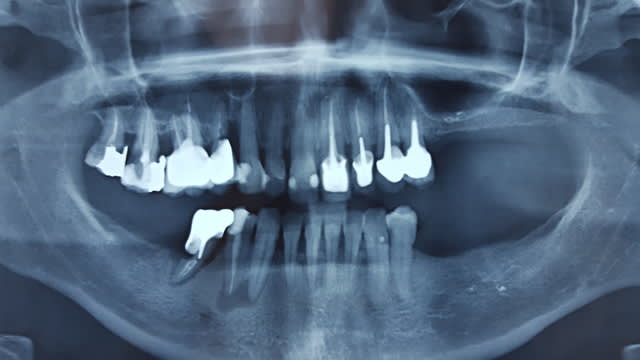

En bonus, je vous gratifie de la panoramique après traitement d'une patiente CMU.

Les couronnes solidaires de 15 et 16 viennent d'être posées.

La couronne de 45 aussi, support de crochet de stellite bancal, en mobilité terminale...

Vous avez mal sur 16/17, c'est rien, y'a rien.